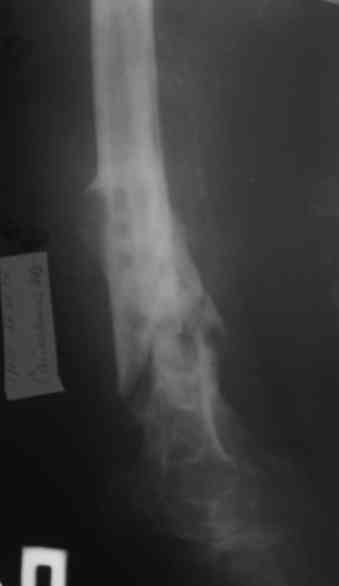

Уважаемые коллеги! Пациент лечился по поводу перелома н/3 бедра 1 год назад.

В настоящий момент: Несросшийся перелом н/3 правого бедра. Остеомиелит, свишевая форма.Контрактура коленного сустава.

Не факт, что поможет. Вариант классический в стране ГА Илизарова - санация - удаление всего мертвого с резекцией и потерей длины - аппарат для сращения и восстановления длины в один или два этапа (судя по ситуации). Многократно опробован. Тем паче, что остеомиелит хоть и травматический (операционный), но не канальный-тотальный (от штифта), а достаточно локален (от пластины).

Привет. Я имел в виду предложенную Вами программу лечения. Поражение кости остеомиелитическим процессом (судя по рентгенограммам) не канальное - когда спейсер можно поставить в канал после санации на какое-то время, а по всей окружности кости - когда придется делать спейсер в виде простой "болванки на арматуре). Вероятнее всего при хорошей санации получится дефект и укорочение. При втором этапе (как я понял, вы планируете БИОС) не факт, что восстановите длину и не "полыхнет" инфекция. Поэтому и предложена другая программа. Ваше право выбора - удачи на сложном пути избавления больного от ятрогенного о\миелита. Если проинформируете, что получилось, спасибо.